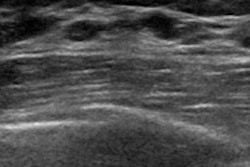

The women were divided into two sets, 330 for a training set and 147 for a validation set. The team reviewed ultrasound and mammography features. The clinical model included lesions that presented as a mass at ultrasound without microcalcification and no comedonecrosis at biopsy. This was used to identify low-nuclear-grade DCIS.

The team wrote that low-nuclear-grade DCIS lesions manifesting as a mass at ultrasound without microcalcifications at mammography and no comedonecrosis at biopsy were not upgraded at surgery.